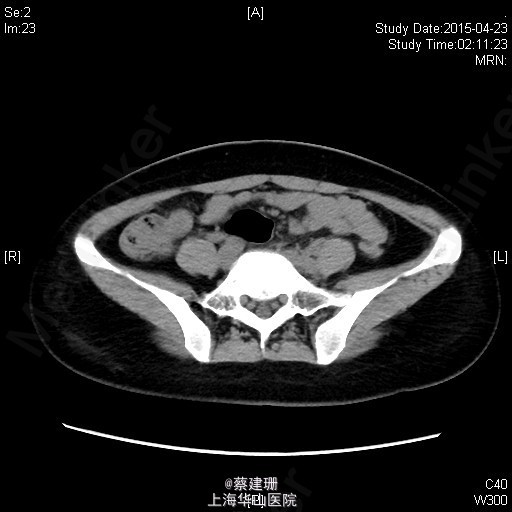

急性阑尾炎(粪石?)伴局限性腹膜炎

患者 女性 24岁,因“转移性右下腹痛一天余。”入院。患者一天前无明显诱因下出现中上腹疼痛,无恶心呕吐,无腹泻。10小时前疼痛转移至右下腹,原先中上腹疼痛缓解,无发热无腹泻。患者未予重视,后疼痛难忍于今日凌晨至我院急诊就诊,血常规示:WBC:18.63*10^9/L,我院B超示:右下腹见肠段局限性扩张,炎性病灶待排。肝胆胰脾肾未见明显异常,双输尿管未见扩张。我院CT示:阑尾增大壁增厚内见高密度影及低密度气体影,符合阑尾炎改变,盆腔少量积液。患者拒绝行急诊手术,故予以保守治疗,患者症状未缓解,右下腹疼痛加重。为行进一步诊治,收入院。

全身皮肤粘膜未见异常,无肝掌,全身浅表淋巴结无肿大。腹平坦,腹壁软,右下腹压痛,伴有肌紧张及反跳痛,麦氏点压痛(+),肝脾肋下未触及,肝肾脏无叩击痛,肠鸣音4次/分。 辅助检查:血常规示:WBC:18.63*10^9/L,N:89%。我院B超示:右下腹见肠段局限性扩张,炎性病灶待排。肝胆胰脾肾未见明显异常,双输尿管未见扩张。我院CT示:阑尾增大壁增厚内见高密度影及低密度气体影,符合阑尾炎改变,盆腔少量积液。

入院后诊断:急性阑尾炎伴局限性腹膜炎。完善相关检查,全麻下行腹腔镜下阑尾切除术。术后恢复可,伤口无明显渗出,予以出院。